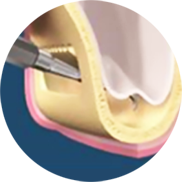

고난도 상악동 거상술

오스카55플란트치과의 뼈이식 임플란트(상악동 거상술) 무엇이 특별한가요?

오스카55플란트치과의 뼈이식 임플란트(상악동 거상술) 무엇이 특별한가요?

디지털 장비를 통한 정밀진단

대학병원급 재료 및 장비

100% 정품 임플란트 사용

고난도 상악동 거상술 수술 과정

STEP 01

디지털 정밀 진단

STEP 02

상악동 점막 거상

-

STEP 03

골이식

-

STEP 04

골생성 확인

-

STEP 05

임플란트 식립